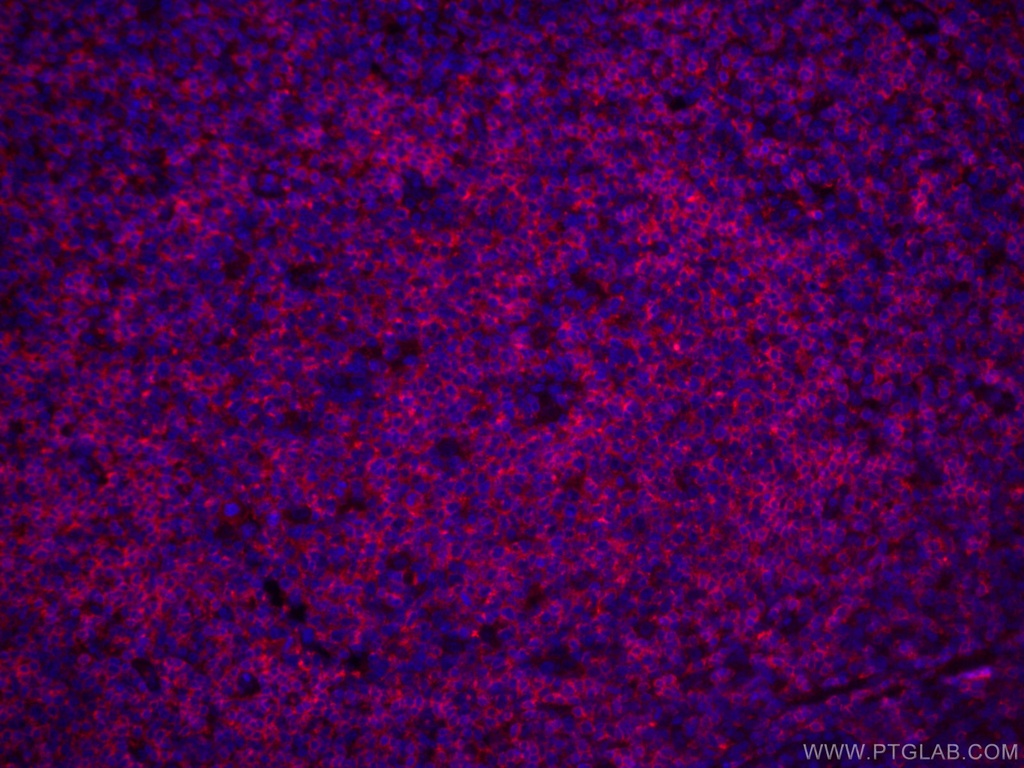

CoraLite®594-conjugated CD22 Monoclonal antibody

Application: IF